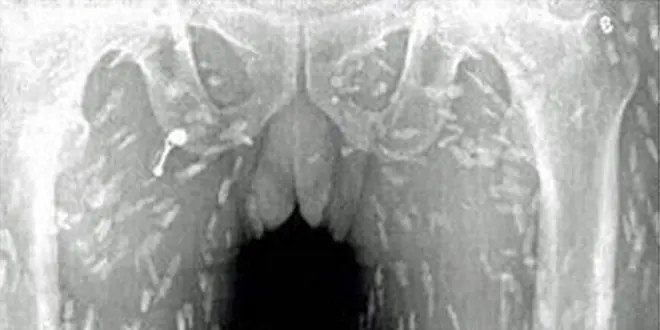

Les clichés versés à charge des sashimis sont, effectivement, très similaires à ceux d'articles scientifiques sur la cysticercose (voir ci-dessous).

Cliché extraits de : Extensive brain and muscular cysticercosis. T. Bejoy et K. Thamburaj, Neurology 2006; doi:10.1212/01.wnl.0000196639.85454.81